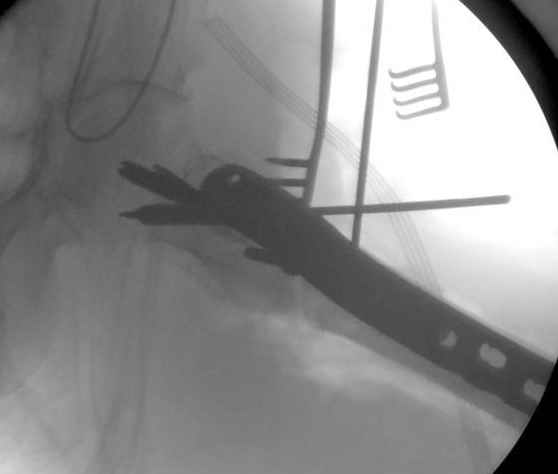

Применили проксимальную Synthes Locking plate, из-за множественных фрагментов посчитали более приемлемым в этом случае (клиника университетская, резиденты должны имет возможность созерцать разные варианты остеосинтеза).

Также старался минимизировать доступ на уровне перелома с субвастус доступом, диафиз фиксирован перкутанно, не стали гонятся за малым вертелом, как смог зафиксировал.